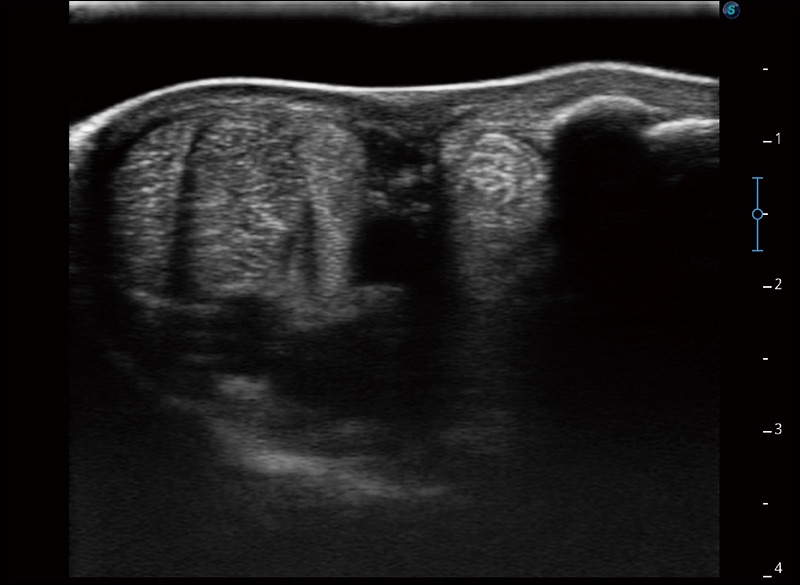

扩展成像

支持线阵和凸阵探头,一键操作即可获得更宽的图像视野

穿刺针增强

高清显示穿刺进针情况